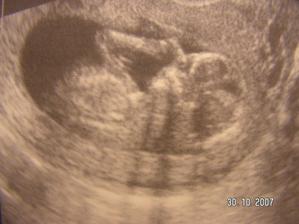

Tak jsme zpět z poradny.Jestli to bude kluk nebo holčička nevíme,protože miminko překřížilo nožky a nechtělo se ukázat.Za to na mamku krásně mávalo,tak to pan doktor zvěčnil-fotka je v albíčku.Měříme už 11cm!!!Zítra - 14.11. jdeme na tripple testy a taky na kontrolu,mamce totiž začalo nějak tvrdnout bříško,tak to pan doktor raději zkontroluje.Snad je všechno v pořádku.///Tak dneska 14.10.-na kontrole všechno v pořádku,jen placenta je trochu moc dole,ale to by se mělo do dvou měsíců upravit,mimi je o pět dní menší,ale krásné.(viz. foto).Dostali jsme magnézko na to tvrdnutí.Nabrali mi krev na tripple testy,tak se bojím,aby to bylo v pořádku.///Tak na testech jsme měli nakonec něco mírně zvýšené,ale celkem ještě v normě,tak doufám,že 12.12. na velkém genetickém UZ bude všechno v pořádku.A třeba se už konečně dozvíme,co to vlastně čekáme.///Tak jsme byli na genet.UZ-všechno je naprosto v pořádku!!!Mimi váží 360g a měří 25cm.Jsme 20+5tt.A víme,co to bude!Holčička!!!///Narazila jsem na úžasný kočárek,byla jsem z něho tak unešená,že jsme ho malé Fazolce museli pořídit.///7.1.-KO v poradně.Princezna má už 633g!!Všechno je v pořádku.Příští týden na cukrovkový test-FUJ!Můj váhový přírustek zatím 4,5kg-24+6tt.///Včera-4.2. kontrola v poradně.Všechno v pořádku.Vážíme 1255g a měříme přes 30cm.Můj váhový přírůstek - 29.tt.-asi 5,5 kg.///3.3.2008-velký UTZ,všechno v pořádku,akorát mám špatný krevní obraz,takže budeme zobat železo.Můj váhový přírůstek 7kg-33.tt.////